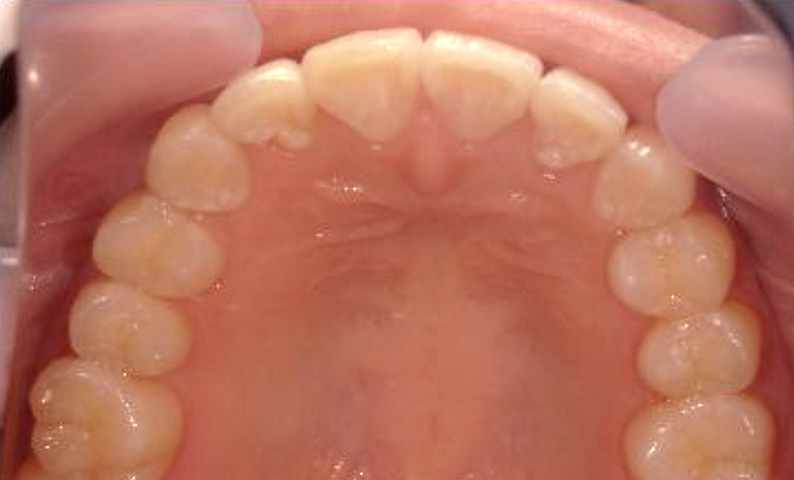

症例_005 上下顎の部分矯正

治療期間:11ヶ月金額:54万円+税女性前歯のガタガタ捻転歯

| Before | After |